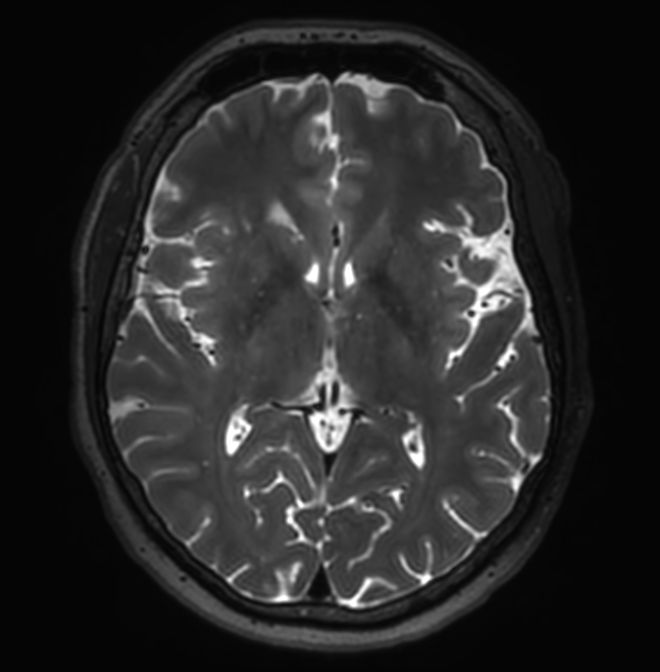

3D VIEW - T2w FLAIR (axial reformat)